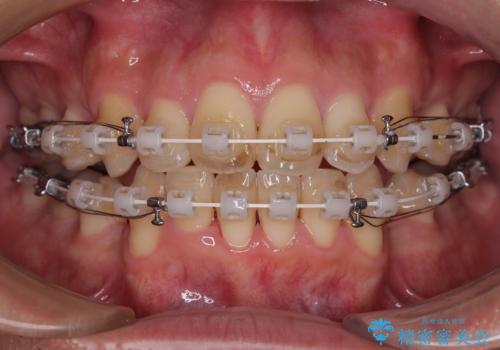

使用した装置は、透明感のあるプラスチックブラケットと白くコーティングされたワイヤー。

金属の装置に比べて目立ちにくく、治療中も自然な見た目を保ちながら矯正を行うことができました。